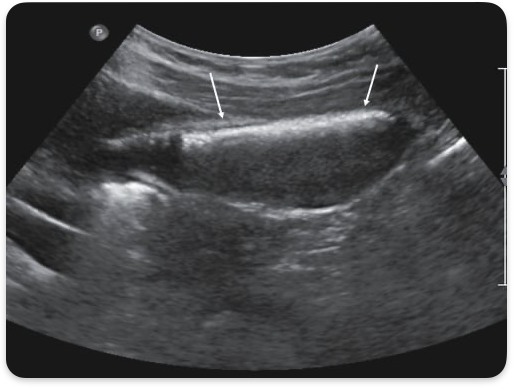

WES sign

GB completely filled w/ stones. Only anterior wall visualized

Cholelithiasis, gallstones